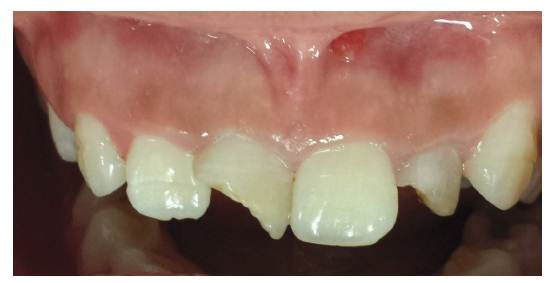

El trauma dentoalveolar (TDA) se define como una lesión de extensión e intensidad variables de origen accidental o intencional; es causado por fuerzas que actúan sobre el órgano dental y los tejidos que le rodean, pudiendo ser observadas o diagnosticadas a simple vista o con la ayuda de la radiografía (foto 1 y 2). Siempre debe ser considerado como una situación de urgencia que debe diagnosticar y tratar rápida y certeramente al odontólogo general integral 1. Sin embargo, su manejo es una fuente constante de dificultades para el clínico, debido a la complejidad del diagnóstico y tratamiento adecuado 2, entendiendo que el pronóstico dependerá de un rápido y adecuado tratamiento 3)-(5.